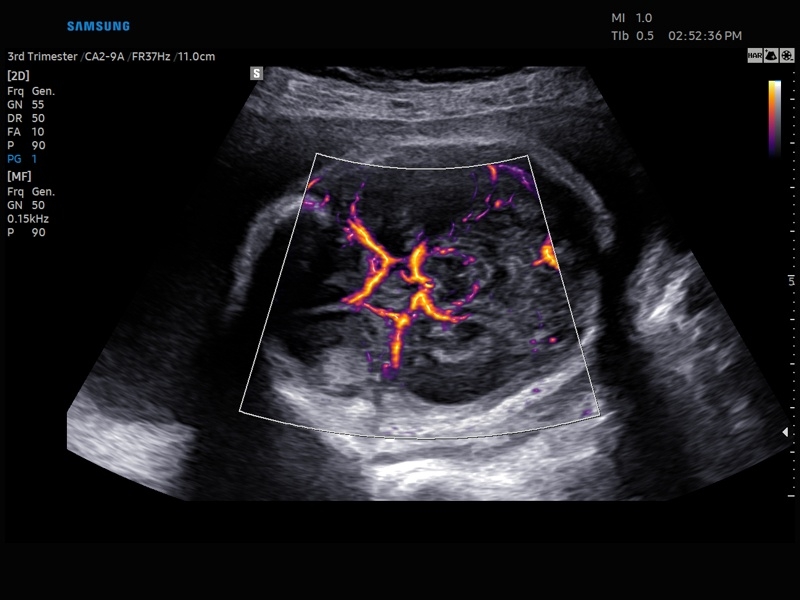

• Цветной, энергетический и направленный энергетический допплер

• Технологии визуализации: MV Flow, LumiFlow, SEE Stream, Panoramic

• Модуль MV-Flow – программа (режим), позволяющая визуализировать кровоток в микроциркуляторном русле с высоким разрешением без использования контраста.

• Модуль LumiFlow – программа отображения кровотока с объемной графикой для лучшего понимания архитектоники сосудистого русла.

• Модуль MV-Flow - программа (режим), позволяющая визуализировать кровоток в микроциркуляторном русле с высоким разрешением без использования контраста.